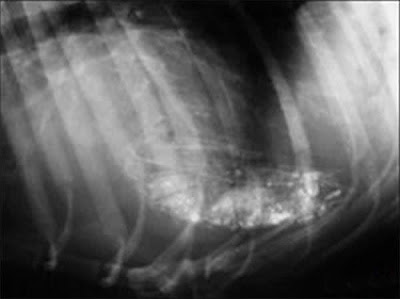

Toys, nails, cell phones, there is an incomplete list of items that are found in the stomachs of four-legged friends